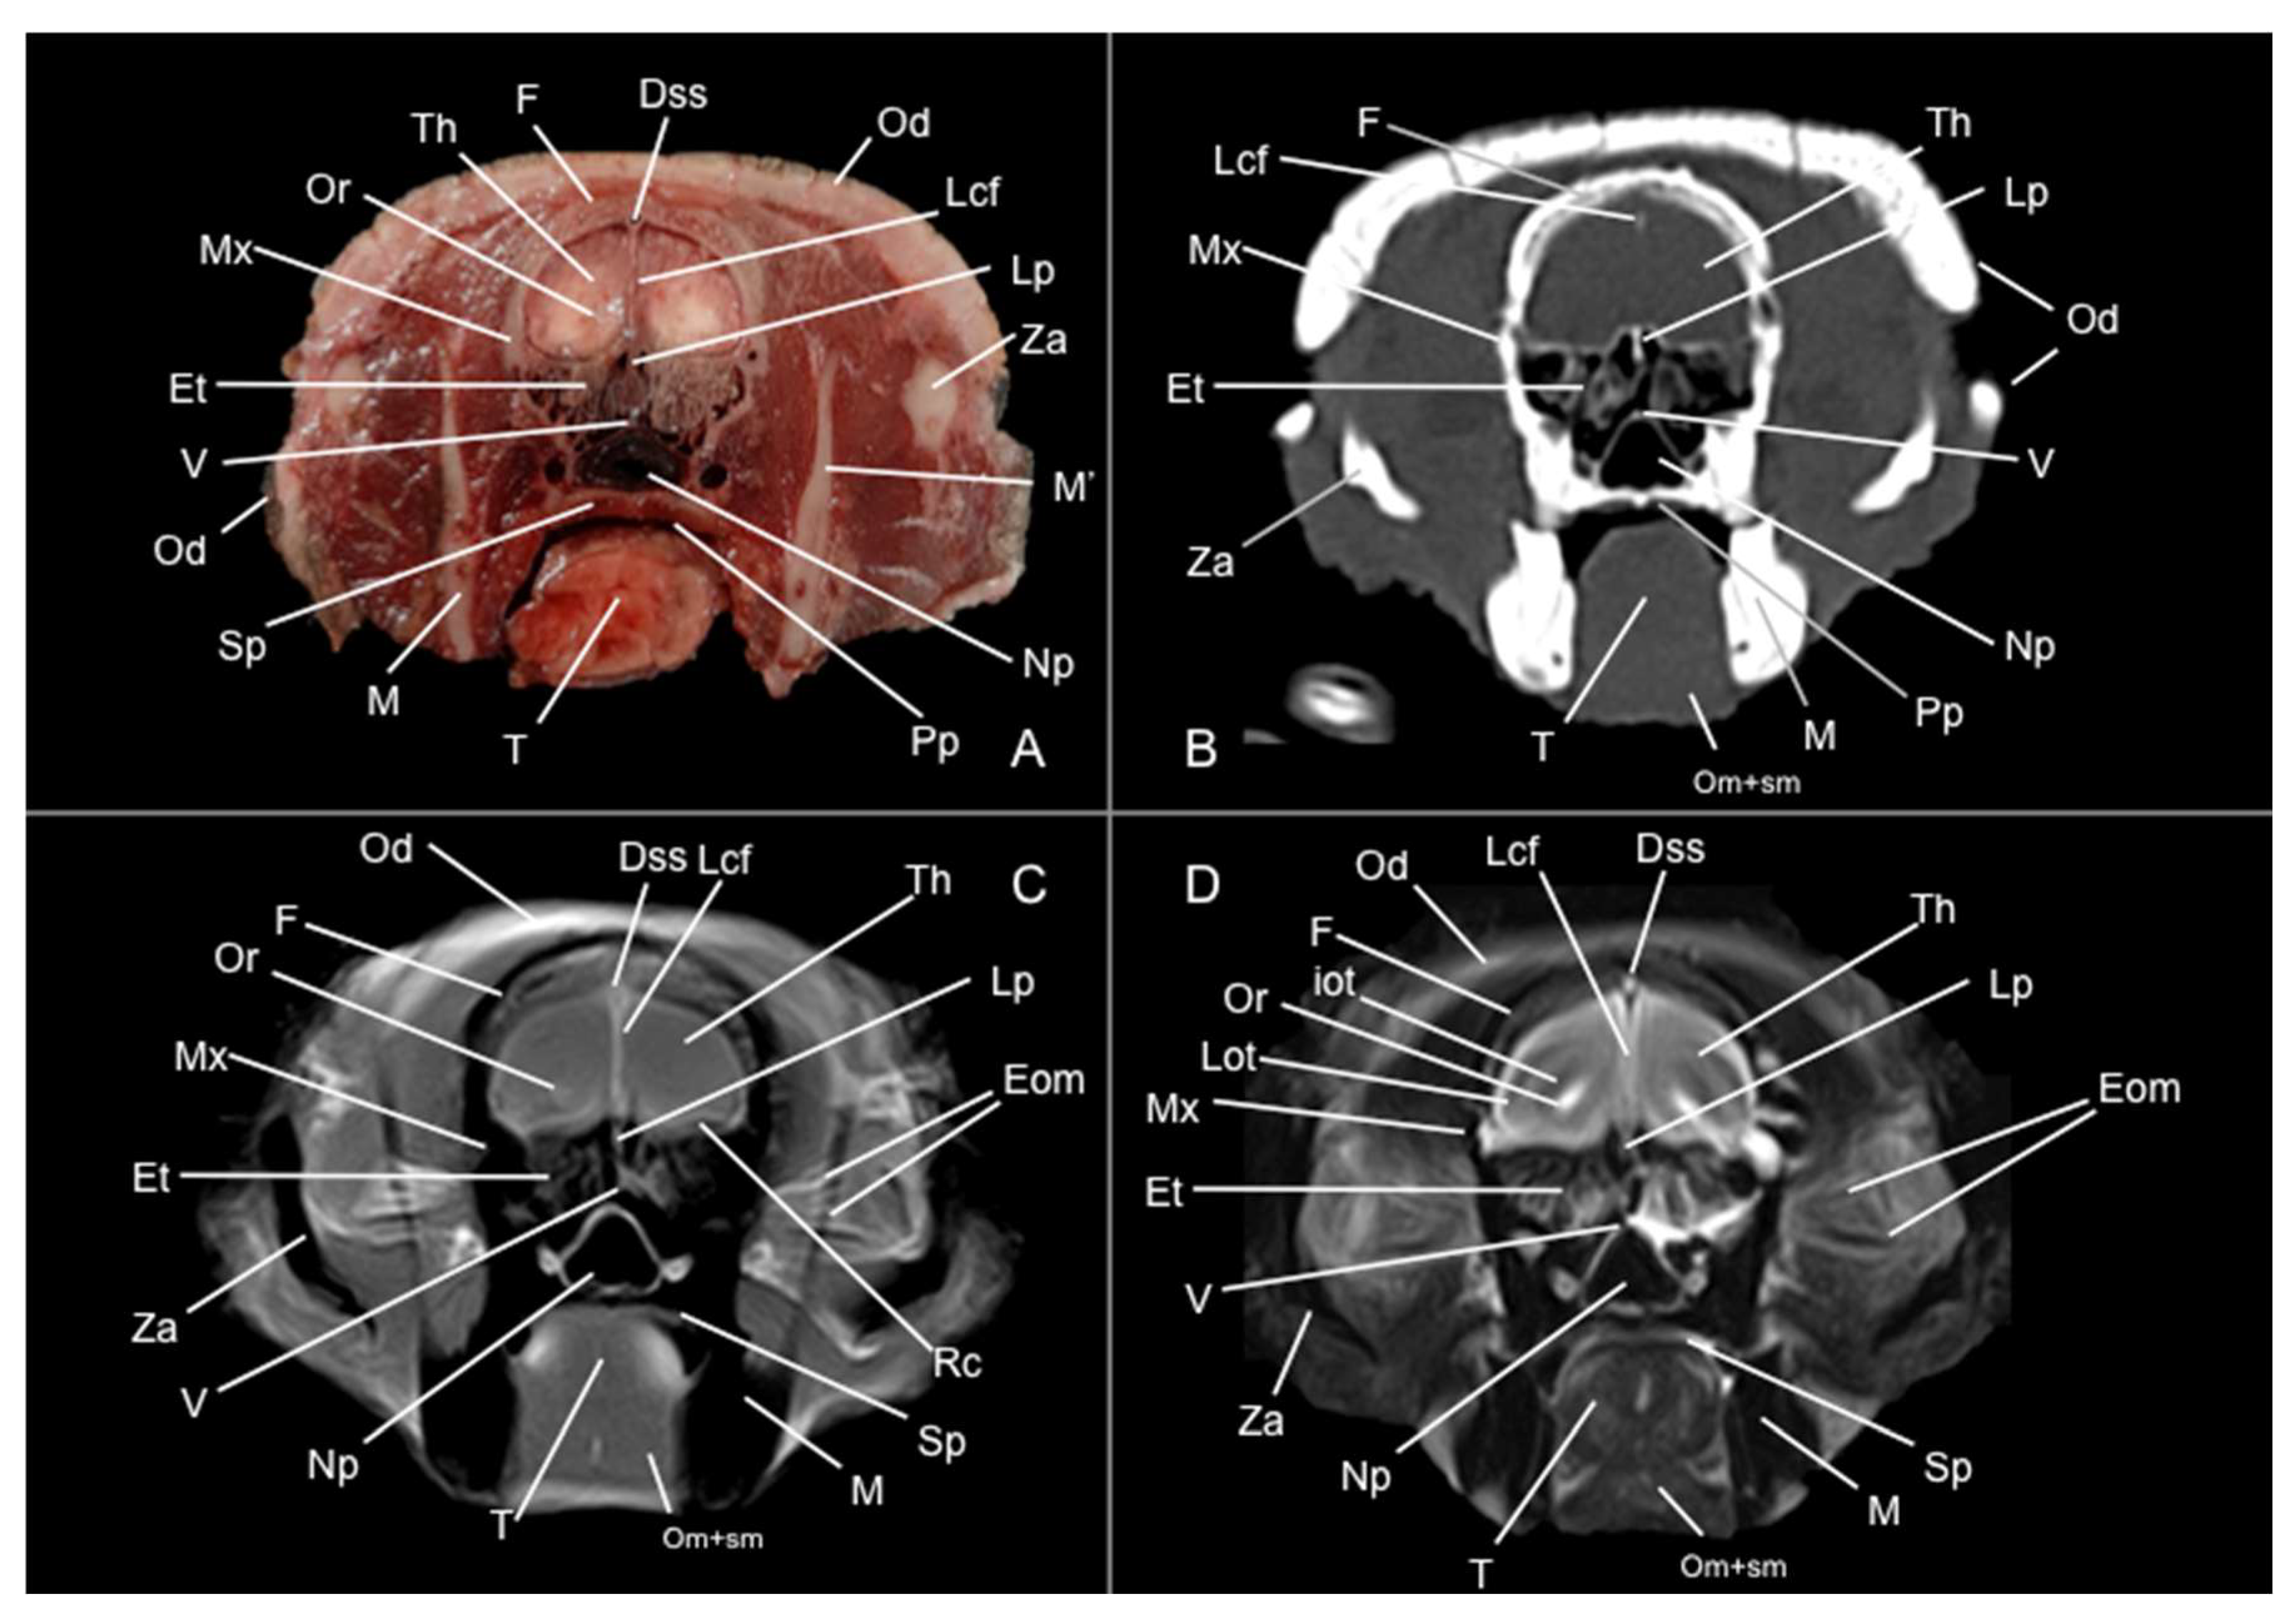

3.1. Anatomical Sections

3.2. Computed Tomography Study

3.3. Magnetic Resonance Imaging (MRI)